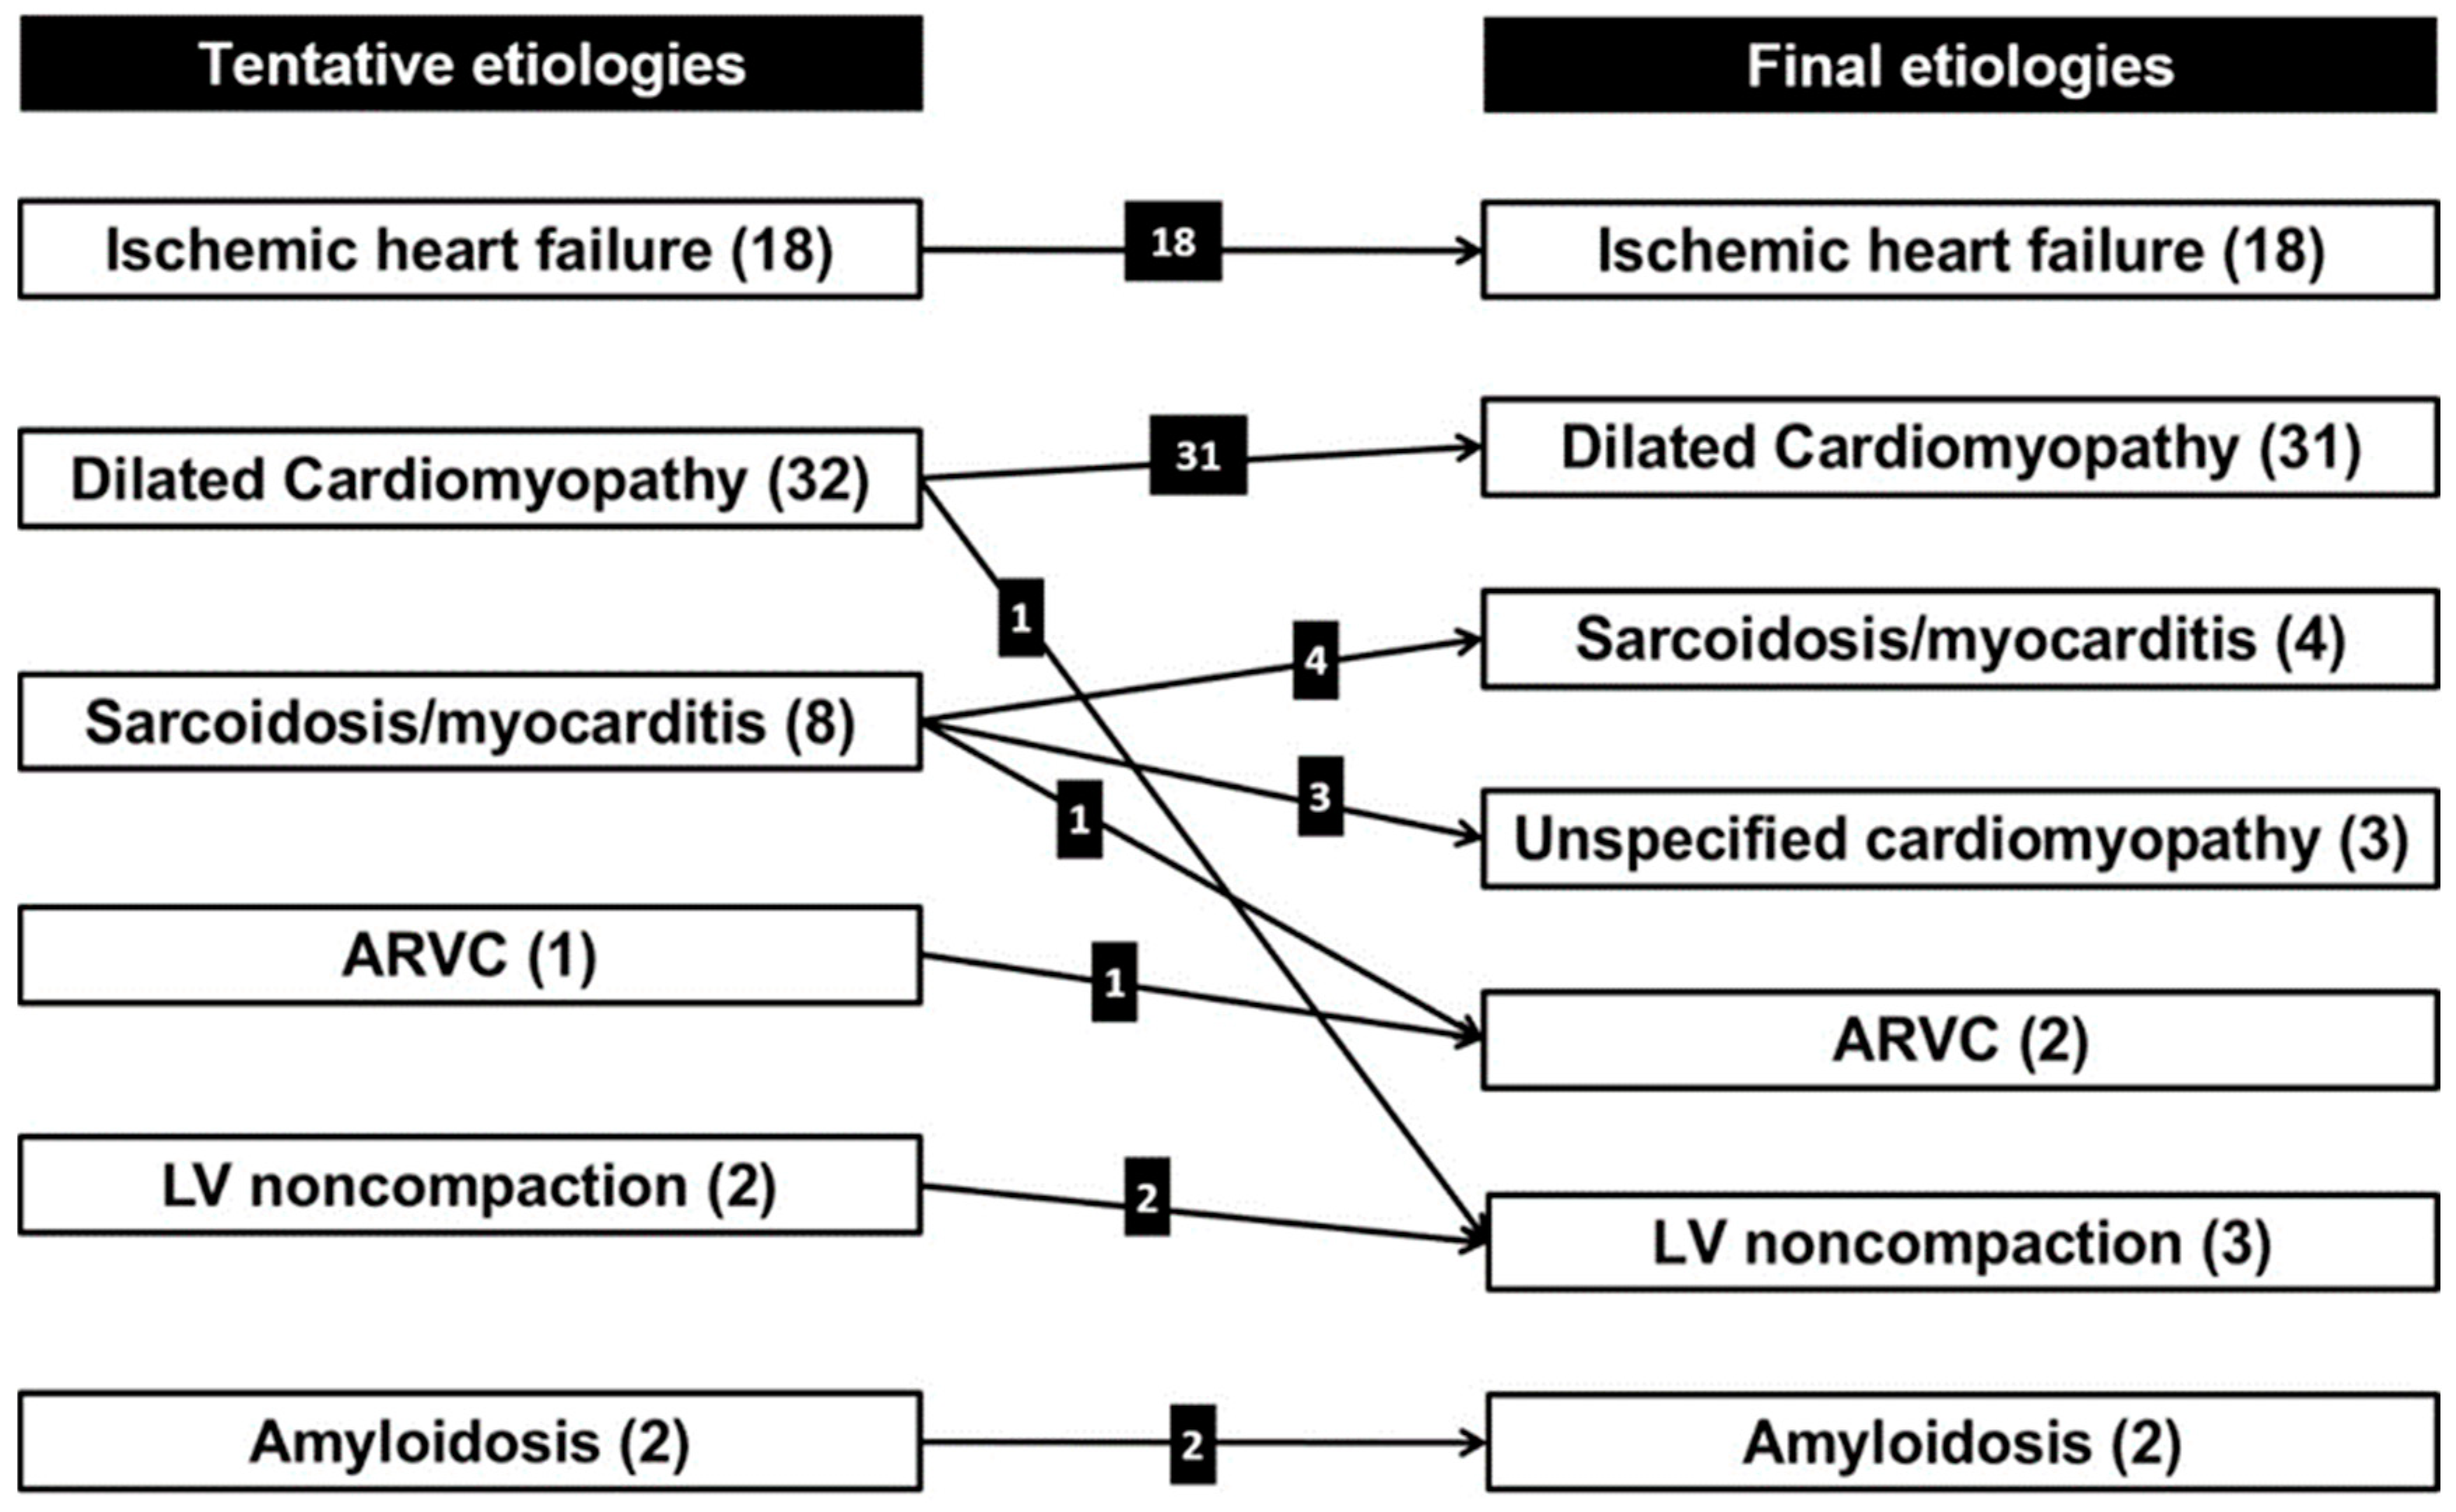

3.5. Final Etiologies of HF from Clinical Decisions and Concordance Between Tentative and Final Etiologies